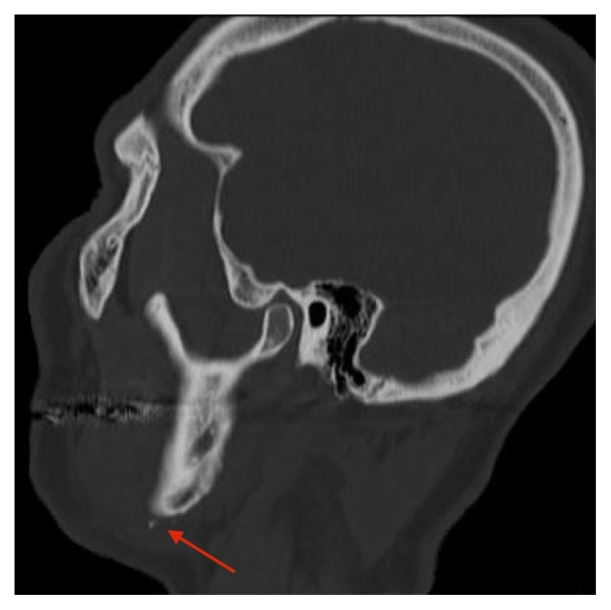

Traumatic Facial Artery Dissection from Chinstrap Injury: A Case Report.

Abstract Image